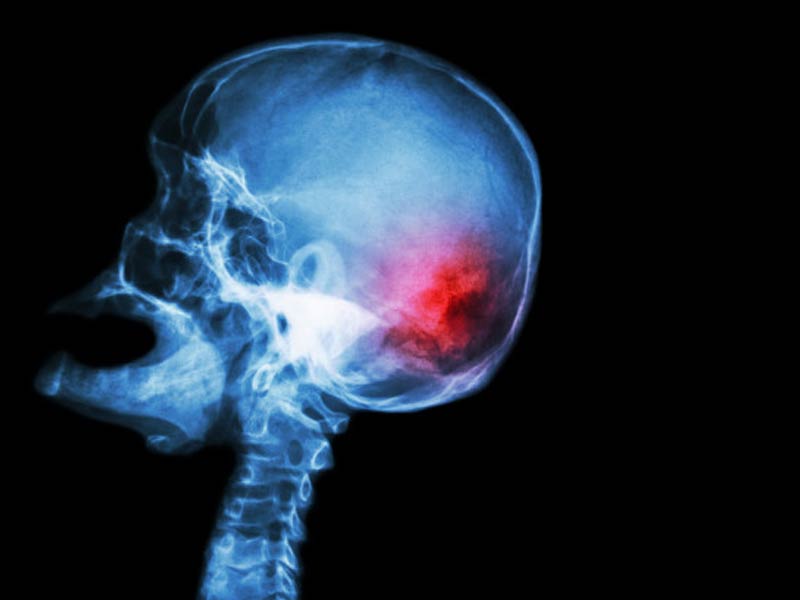

O aneurisma cerebral e o AVC são doenças graves que atingem o sistema nervoso central e, muitas vezes, seus sintomas causam confusão entre a população. O aneurisma é caracterizado pela dilatação anormal de uma das artérias que irrigam o cérebro. Com a parede do vaso fragilizada, o aneurisma pode vazar ou estourar a qualquer momento.

O aneurisma cerebral e o AVC são doenças graves que atingem o sistema nervoso central e, muitas vezes, seus sintomas causam confusão entre a população Istvan Brecz-Gruber/Pixabay